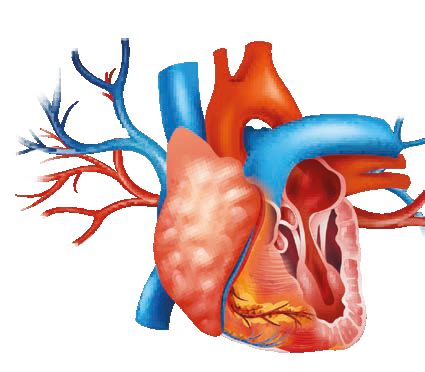

Régulez votre tension artérielle

Pour prévenir les risques liés à une tension artérielle élevée, le Laboratoire NaturoScience a conçu un complément alimentaire à base de 3 plantes reconnues pour renforcer le système cardiovasculaire et favoriser le retour d’une tension normale.

En France comme dans tous les pays industrialisés, les problèmes cardiovasculaires représentent la première cause de mortalité.

S’il y a certains facteurs de risques face auxquels nous sommes impuissants (l’âge, le sexe ou l’hérédité), il y en a d’autres, heureusement, sur lesquels nous pouvons agir. Hypertension artérielle, excès de cholestérol, excès de sucre dans le sang (hyperglycémie) peuvent être maîtrisés en modifiant nos habitudes de vie (alimentation plus saine, exercices physiques…) et en ayant recours aux solutions d’origine naturelle appropriées.